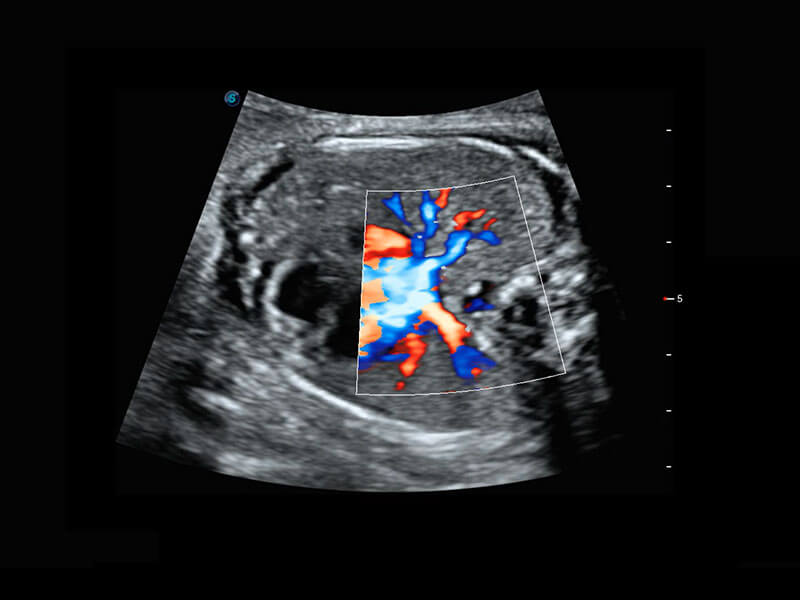

P60搭載寬頻帶線(xiàn)陣探頭、寬景成像、彈性成像技術(shù),為您提供乳腺應(yīng)用方案。P60支持高頻相控陣探頭、線(xiàn)陣探頭、腹部高頻探頭、腹部微凸探頭等,豐富的探頭群搭載敏感的彩色血流成像,適用于新生兒多種臟器檢測(cè)要求,滿(mǎn)足新生兒篩查需求。

新生兒肝血管癌

新生兒脊髓圓錐

新生兒心臟